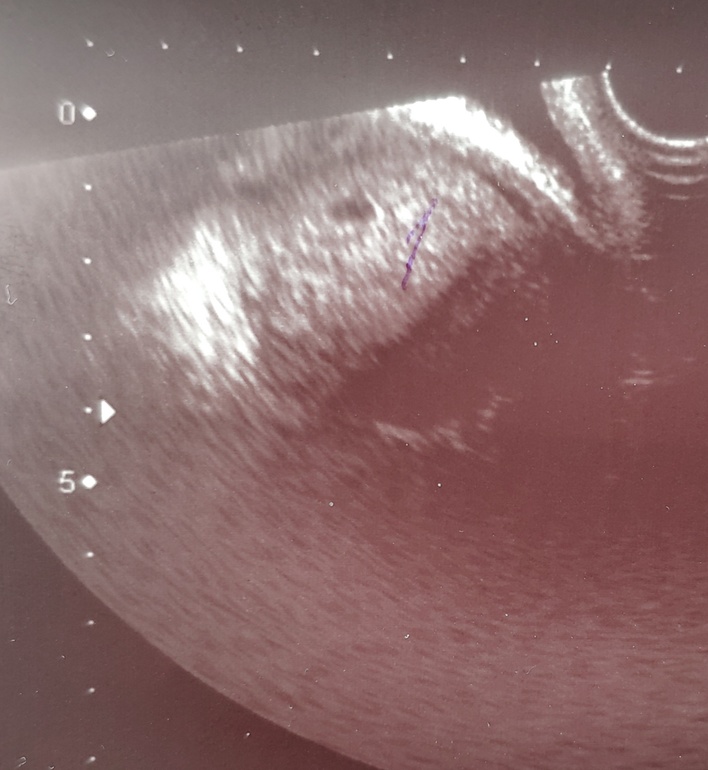

Первое УЗИ 💞

Сегодня 5 недель и 1 день акушерский срок, переносили одну пятидневочку🤰 Сходили на УЗИ, малышка прикрепилась по передней стенке. Я не спросила и узистка не сказала и не написала про желточный мешочек. Сижу смотрю фото и мне кажется, что в пя два пузырика😅 Через две недели опять на УЗИ